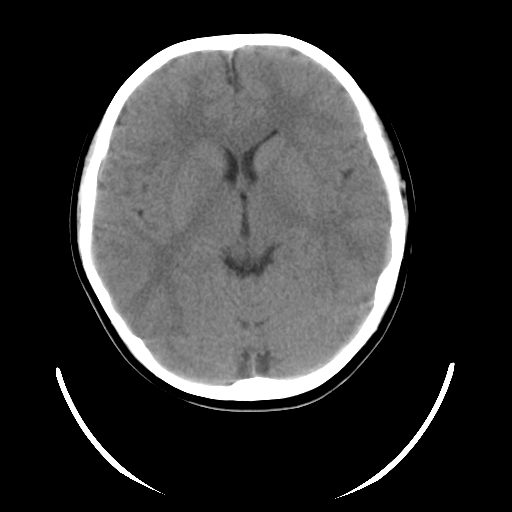

标题: PED3080:女,6岁,头痛、呕吐一天。 [打印本页]

女,6岁,头痛、呕吐一天。

颅脑ct平扫未见明显异常。

头颅ct平扫未见明确异常,随诊复查。